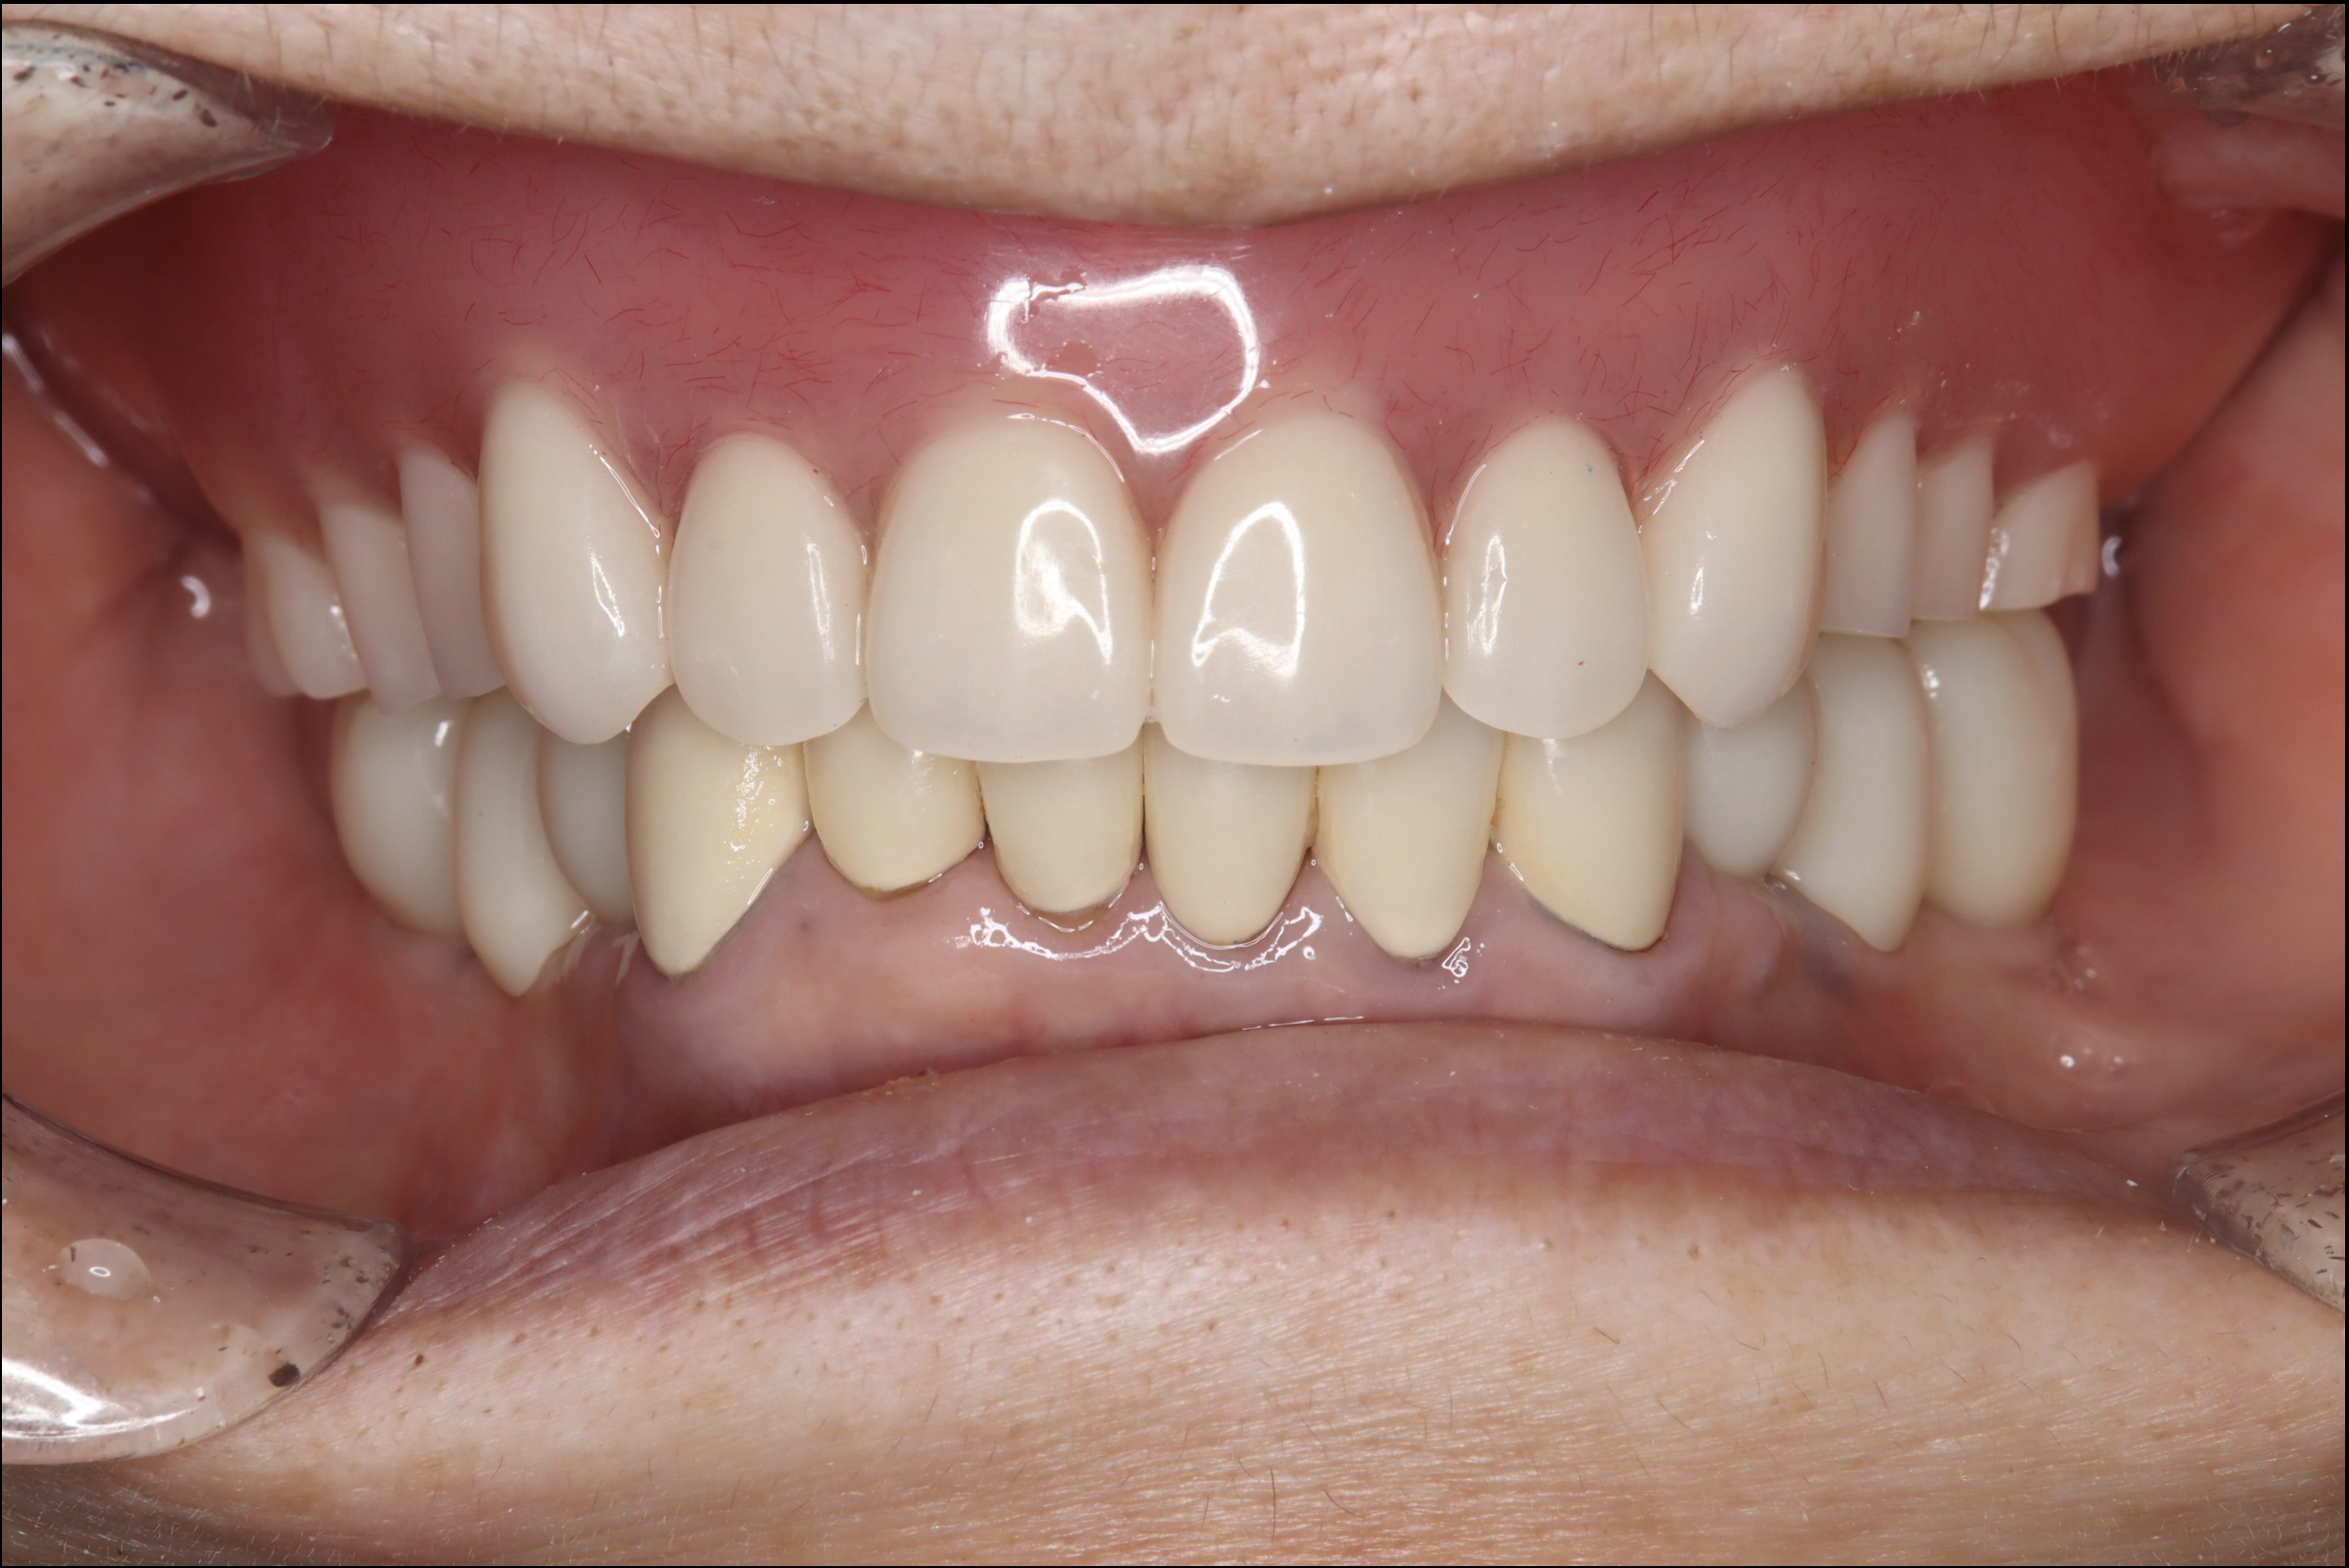

歯がボロボロですが見てもらえますか?

-

A

当院では長年の放置により口腔内がボロボロになってしまった方など様々なお悩みをお持ちの方でも対応可能です。その人にあった治療方法をご提案させていただきます。

ボロボロの口腔内から改善をされた方の症例がございますので症例集をご覧ください。